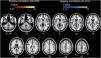

ResultsGroup comparisons of seed-based connectivityThe left A1 and DLPFC connectivity maps of the tinnitus (Fig. 1A and Fig. 2A) and control (Fig. 1B and 2B) groups were compared using a two-sample t-test. The statistical significance was set at a false discovery rate of p<.05 using cluster-based inference. Both maps showed significantly increased positive and negative connectivity in the tinnitus group compared with the control group. There was no significantly increased positive or negative connectivity in the healthy controls compared with the individuals with tinnitus. Significantly increased left A1 positive connectivity was observed with the left middle temporal (BA21), cingulate, and postcentral areas (Fig. 3A and Table 2). Significantly increased negative left A1 connectivity was observed with the left superior, middle, and medial frontal and angular (BA39) areas as well as right cerebellar areas (Fig. 3B and Table 2).

Averaged left A1-based functional connectivity maps of the (A) tinnitus and (B) control groups. The first row represents the positive correlation between the left A1 and whole brain, whereas the second row represents the negative correlation between the left A1 and whole brain. The hot colormap represents the brain areas that positively correlate with the left A1, whereas the winter colormap represents the brain areas that negatively correlate with the left A1. For visualization, the left A1-based connectivity maps of all patients or all controls are averaged and thresholded by the z value of |1|. The green area indicates the seed region. The connectivity between the left A1 and bilateral superior, middle, and medial frontal areas, middle and inferior temporal areas, inferior parietal areas, and subcortical areas as well as the right inferior parietal lobule is significantly negative in the tinnitus group (winter colormap in A) and not in the control group (gray color in B). The connectivity between the left A1 and bilateral somatosensory areas (winter colormap in A and B, z=25 and 31) is positive in both groups, but stronger in patients with tinnitus.

Association between tinnitus improvement (ΔTHI) and the left A1-based connectivity maps of the tinnitus group. The hot colormap represents the positive correlation between the ΔTHI and left A1-based connectivity maps. The winter colormap represents the negative correlation between the ΔTHI and left A1-based connectivity maps. Tinnitus improvement was estimated by subtracting the pre-rTMS THI scores from the post-rTMS THI scores. Thus, a low ΔTHI (hot colormap) indicates a good rTMS outcome, whereas a high ΔTHI (winter color map) indicates a poor rTMS outcome. An rTMS outcome is poor when the connectivity between the left A1 and bilateral frontal cortices is similar to that of the control subjects (i.e., stronger connectivity [hot colormap]). An rTMS outcome is good when the connectivity between the left A1 and bilateral temporal cortices is strong (winter color map).